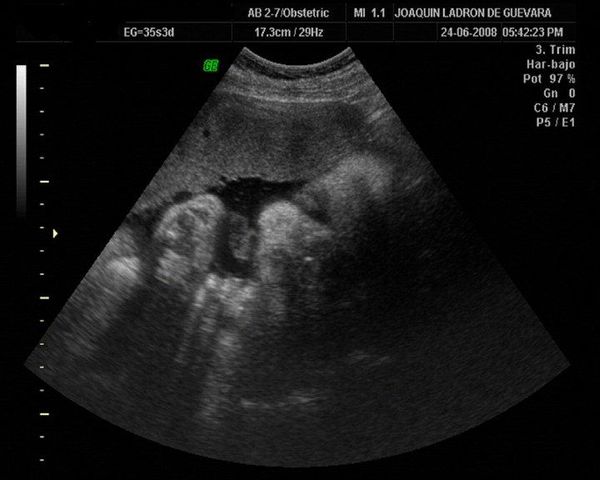

Mi segundo bebe

me hicieron una ecografia donde me mostraron su sexo y sus partecitas completas.